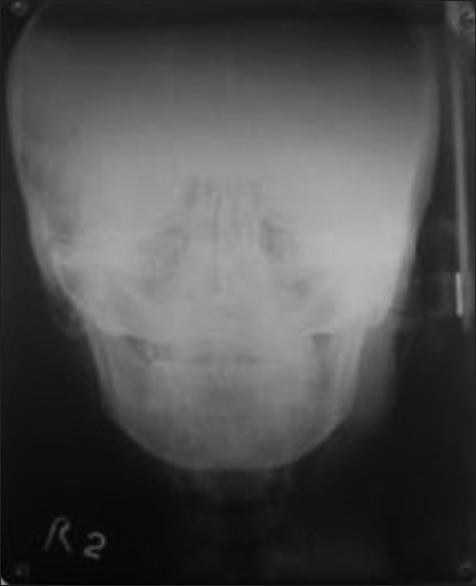

Unilateral condylar hyperplasia is an uncommon condition with unknown etiology which causes overdevelopment of condyle leading to facial asymmetry, mandibular deviation, malocclusion, and articulation dysfunction. Two Indian families with unilateral condylar hyperplasia are presented where the similar abnormality was also detected in one of their parents. The condylar hyperplasia in these two families indicates that mandibular condylar hyperplasia could be genetic in origin.

单侧髁突增生是一种病因不明的罕见病症,它会导致髁突过度发育,进而引起面部不对称、下颌偏斜、错牙合畸形及关节功能障碍。本文报告了两个患有单侧髁突增生的印度家族,在他们的一位家长中也检测到了类似异常。这两个家族中的髁突增生表明下颌髁突增生可能起源于遗传。